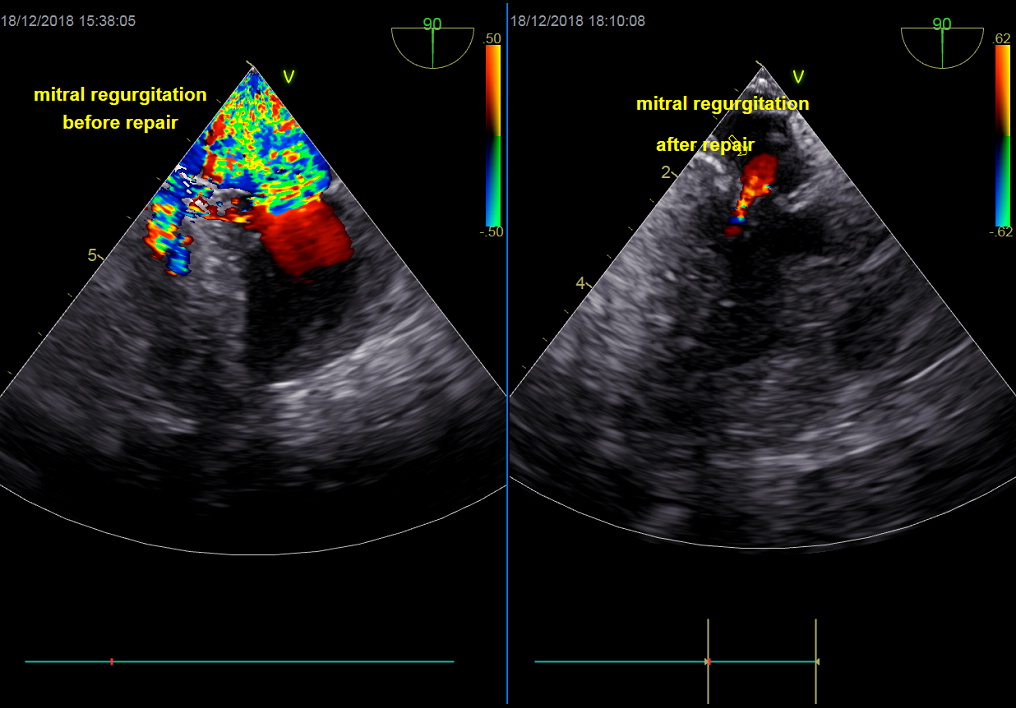

18. Control transoesophageal heart-scan: the mitral valve coaptation, residual mitral regurgitation, systolic function, ventricle blood volume and presence of gas are checked.

Once the mitral valve is repaired and the new chordae are set in place, the mitral prolapse is diminished if not abolished, the valve coaptation is appropriate and the mitral regurgitation is markedly reduced. The left atrium has an amazing plasticity which allows it to reduce to a normal size in sometimes no more than a week post-operatively if the tissue is still healthy enough and if surgery hasn’t been performed to late.

About 80% of the dogs will stop medication after 3 months. A diminution of the heart cavities will be observed, a significant loss of mitral regurgitation that will become moderate or inexistent, enabling your dog to live normally without having breathing difficulties or being tired.

Pictures on the right: Mitral valve repair performed by Dr JH Bozon. Top : Peroperative Transoesophageal Echocardiographye (Dr Sabine Bozon). Bottom : Post-operative trans-thoracic Echocardiography (Dr Sabine Bozon)